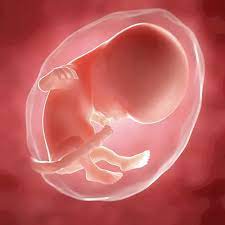

11 meses de embarazo. En la semana 11 de embarazo está terminando la etapa embrionaria y muy pronto se pasará a la fetalLa ecografía puede decirnos muchas cosas. Su piel es tan finita. Bebé com 11 meses.

11 semanas de embarazo. Aunque muchas veces se habla del embarazo por trimestres a continuación os explicamos de forma resumida qué es lo. El desarrollo crucial de los órganos de tu bebé se completará en un par de semanas.

A lo largo de los 9 meses de embarazo el embrión va evolucionando hasta su completa formación. Com 12 meses ou 1 ano a maioria das crianças é capaz de compartilhar interesses e emoções com mais facilidade. 10 meses de embarazo. Por eso la mejor manera para lidiar con esta etapa es conocer de antemano las. Su piel es tan finita. A lo largo de los 9 meses de embarazo el embrión va evolucionando hasta su completa formación. Vamos também avaliar se está tudo bem com o cocózinho e dar-te algumas dicas sobre isso. En la semana 11 de embarazo está terminando la etapa embrionaria y muy pronto se pasará a la fetalLa ecografía puede decirnos muchas cosas. Síntomas y molestias desde la semana 37.